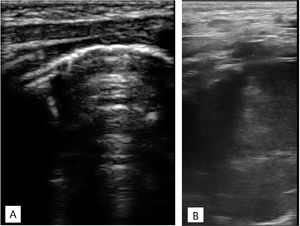

TAC torácica con administración con contraste intravenoso. Masa en mediastino posterior de 4,6×4,3×6,3cm con realce heterogéneo y pequeñas calcificaciones en su interior que ejerce efecto masa desplazando estructuras adyacentes y comprimiendo el lóbulo superior derecho. A)Corte coronal. B)Corte sagital.